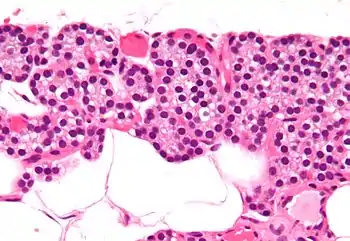

Célula principal paratiroidea

Las células principales paratiroideas (o simplemente células paratiroideas) son aquellas células encargadas de producir la hormona paratiroidea o parathormona (PTH). Forman, junto a las células oxifílicas y a las células acuosas, cada una de las glándulas paratiroides ubicadas en el cuello.